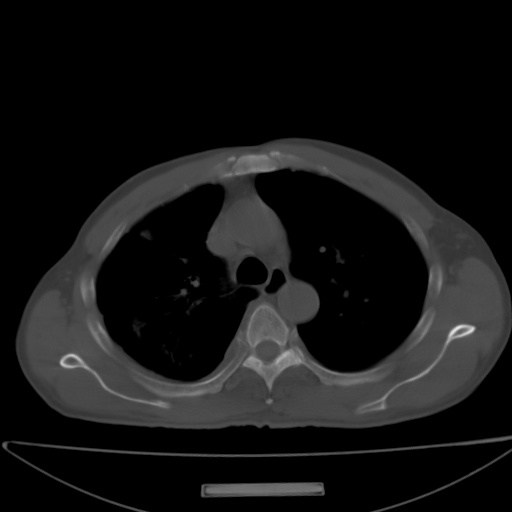

以下是引用jsgdoctor在2008-11-6 22:12:00的发言:[br]右主支气管壁明显增厚,管腔狭窄.考虑为右侧中央型肺癌伴阻塞性炎症\\肺脓肿.

以下是引用zjzjr在2008-11-6 20:25:00的发言:[br]中心型肺ca,合并阻塞性肺炎

以下是引用zsl6918在2008-11-6 19:43:00的发言:[br]右侧中心性肺癌(鳞癌)